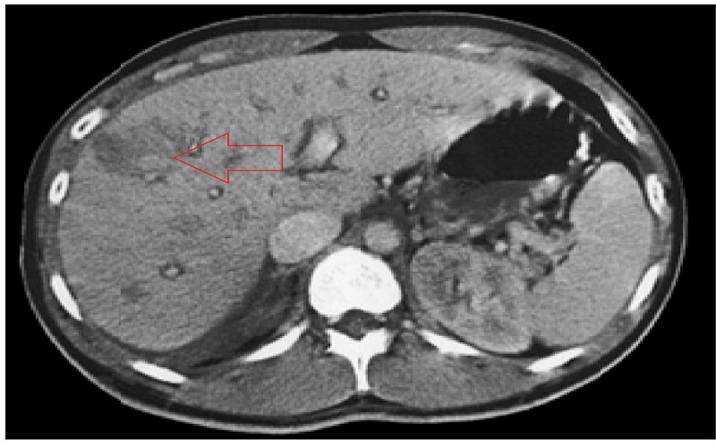

យោងតាមការបង្ហោះផ្សាយលើបណ្តាញសង្គមហ្វេកបុក-Facebook របស់លោកវេជ្ជបណ្ឌិត Dr. Sopheak ជាវេជ្ជបណ្ឌិតជំនាញផ្នែកក្រពះពោះវៀន មានបទពិសោធន៍លើសពី 22 ឆ្នាំ ក្នុងការប្រឹក្សា និងរៀបចំម៉ឺនុយសម្រាប់អ្នកជំងឺបេះដូង ទឹកនោមផ្អែម ជំងឺតម្រងនោម ការផ្ទុកខ្លាញ់ក្នុងថ្លើម និងជំងឺរ៉ាំរៃផ្សេងៗទៀត បានបង្ហាញពីការឆ្លុះបញ្ចាំងពីអ្នកជំងឺម្នាក់ ដែលជាបុរសវ័យ ៥៦ ឆ្នាំ រូបរាងមើលទៅមានសុខភាពល្អ បានមកមន្ទីរពេទ្យដោយសារតែគាត់ជុះលាមកចេញឈាមច្រើនថ្ងៃ។ គាត់បាននិយាយបណ្តើរ សើចបណ្តើរថា<< ប្រហែលជាខ្ញុំកើតឬសដូងបាតទេលោកគ្រូពេទ្យ ខ្ញុំតែបរិភោគអាហារល្អសម្រាប់សុខភាពណាស់ គឺសុទ្ធតែបន្លែ ធញ្ញជាតិទាំងមូល ទឹកដោះគោគ្រាប់ធញ្ញជាតិ មិនបរិភោគសាច់ខ្លាញ់ គ្មានផឹកស្រាបៀរ ឬស្រាទេ>>។ ប៉ុន្តែនៅពេលដែលនៅពេលលោកវេជ្ជបណ្ឌិត បញ្ចូលឧបករណ៍ត្រួតពិនិត្យឆ្លុះចូលទៅ ក្រុមការងារទាំងមូលស្ងាត់មាត់តែម្តង ដោយសារតែពោះវៀនធំរបស់គាត់ពោរពេញទៅដោយដំបៅរលួយ និងមានដុំសាច់ (ប៉ូលីប) ធំៗពណ៌ក្រហមឆ្អៅ ហើយតំបន់ខ្លះមានការផ្លាស់ប្តូររូបរាងទៅជាសណ្ឋានគួរឱ្យសង្ស័យថានឹងវិវត្តទៅជាមហារីក។

ត្រឹមតែមួយជំហានទៀតប៉ុណ្ណោ គាត់គឺនឹងក្លាយទៅជាមហារីកដំណាក់កាលចុងក្រោយ។ ក្រោយពីលោកវេជ្ជបណ្ឌិត ពិនិត្យមើលរបបអាហាររបស់គាត់ឱ្យបានដិតដល់ ខ្ញុំក៏បានយល់អំពីមូលហេតុគឺ៖

មហារីកពោះវៀនធំ គឺជាប្រភេទមហារីកមួយក្នុងចំណោមប្រភេទមហារីកទាំង ៥ ដែលកើតមានច្រើនជាងគេបំផុតនៅកម្ពុជា ហើយករណីភាគច្រើនគឺបណ្តាលមកពីទម្លាប់នៃការបរិភោគអាហារមិនត្រឹមត្រូវ។ក្រោយក្រុមគ្រូពេទ្យបានធ្វើអន្តរាគមន៍ទាន់ពេល កាត់យកដុំសាច់ (ប៉ូលីប) ធំៗចេញ និងតាមដានគាត់យ៉ាងជិតស្និទ្ធ។ ប៉ុន្តែអ្វីដែលធ្វើឱ្យលោកវេជ្ជបណ្ឌិត នៅតែឈឺចាប់នោះគឺ៖ បើសិនជាគាត់បានបរិភោគត្រឹមត្រូវតាំងពីដំបូងមក គាត់នឹងមិនចាំបាច់ជួបប្រទះនឹងការជុះឈាម និងប្រឈមមុខនឹងគ្រោះថ្នាក់មហារីកនៅក្បែរនោះទេ។ ថ្ងៃដែលគាត់ចេញពីមន្ទីរពេទ្យ លោកវេជ្ជបណ្ឌិត បានប្រគល់សៀវភៅមួយក្បាលឱ្យគាត់គឺជា “របបអាហារព្យាបាលគ្រប់ជំងឺ”។ នៅក្នុងនោះមានផ្នែកជាក់លាក់មួយសម្រាប់អ្នកជំងឺពោះវៀនធំមានដូចជា៖